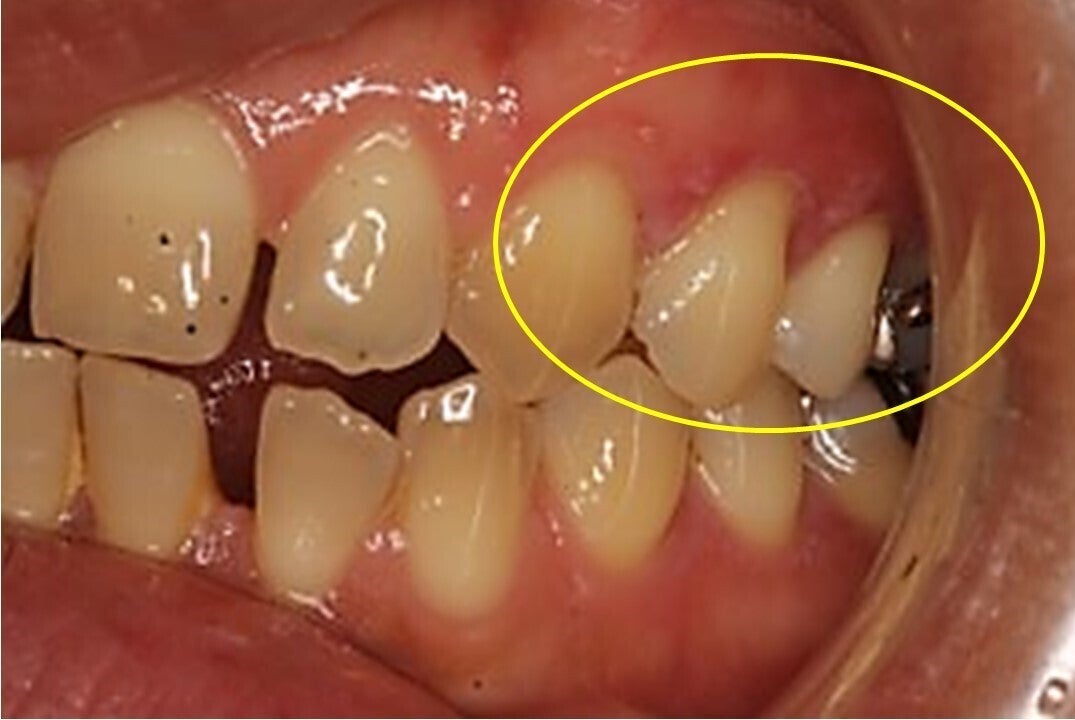

歯ブラシが原因と思われる傷

自分では見えない部分 やり過ぎになってしまう

開業以来、日々の診療の中で、磨き過ぎが原因と考えられる方が多数、来院されます。虫歯も無い、歯周病も無い、しかし、違和感や症状を訴える方がたくさんいらっしゃいます。

よく観察すると、歯ぐきに小さな傷があり、磨き過ぎが原因ではないかと考えました。それから辛抱強く歯みがき指導を行っていくと、大きな処置をしなくても、症状が軽減される方が増えていきました。

右利きの人は左側が磨きやすいので強くなる傾向がある